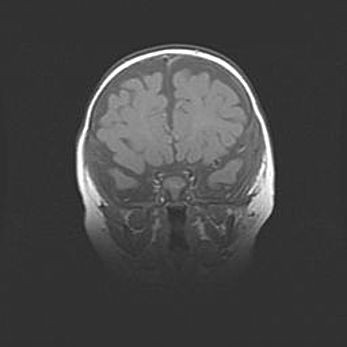

Аномалия Денди-Уокера. Признаки гипоплазии мозолистого тела.

Возраст: 5 месяцев 3 дня

Вес: 5550 г

Пол: мужской

Окружность головы: 39 см

Срок гестации: 40 недель

Аномалия Денди-Уокера – это порок развития головного мозга, для которого характерна триада симптомов: гипотрофия или аплазия червя мозжечка и/или полушарий мозжечка, расширение четвёртого желудочка с формированием ликворной кисты задней черепной ямки, гипертензионная гидроцефалия различной степени.

Гипоплазия мозолистого тела относится к дефектам внутриутробного этапа развития мозговой ткани, возникающим в процессе закладки структур головного мозга, что происходит на начальных этапах развития эмбриона.